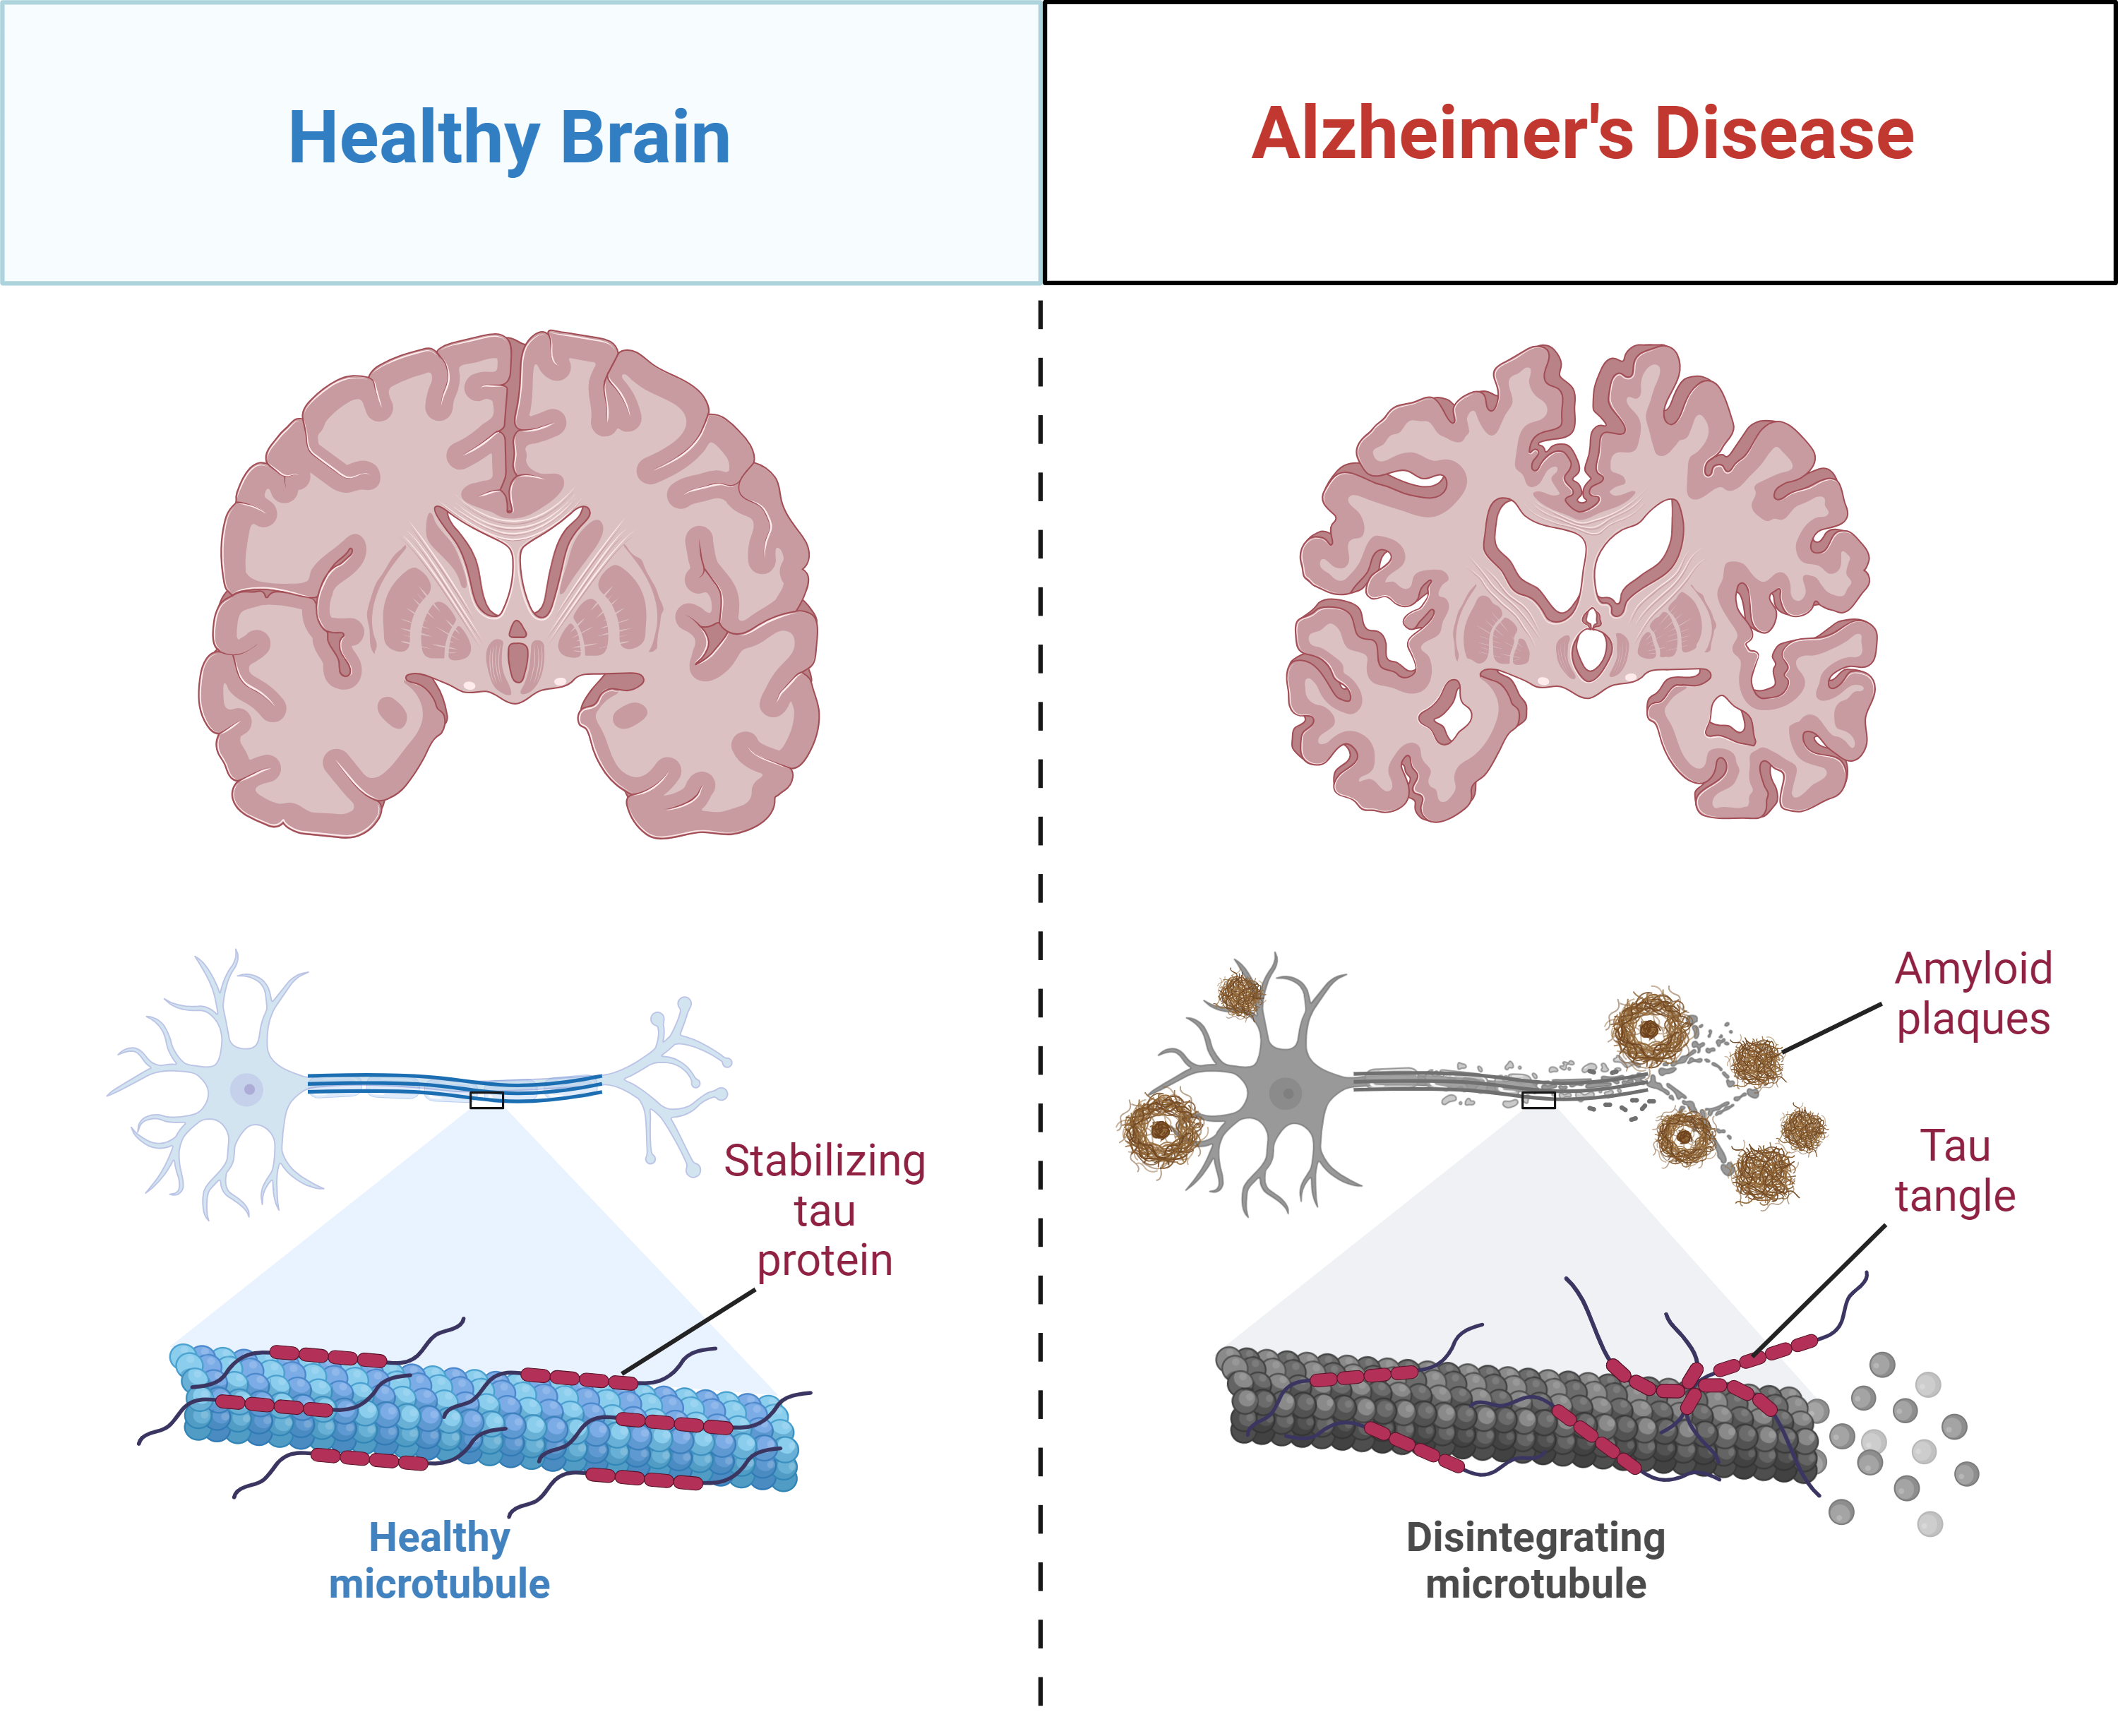

Buildup of Amyloid-Beta and Tau

Dr. Alois Alzheimer first discovered Alzheimer’s after observing dense plaques and tangle-like structures in the brain of a middle-aged patient who had experienced memory loss and other symptoms. Plaques and tangles do appear in the brains of elderly, non-demented individuals—but to observe this pathology in a younger patient was peculiar. Scientists would later come to find that these Alzheimer’s hallmarks are the end-product from a decades-long buildup of two proteins: amyloid-beta (plaques) and tau (tangles). Smaller forms of these proteins, called oligomers, may begin damaging the brain long before any symptoms appear.

Scientists at C2N Diagnostics used their scientific understanding of amyloid-beta and tau in Alzheimer’s to create a first-of-its-kind blood test with early support from Alzheimer’s Disease Research program. Learn more.